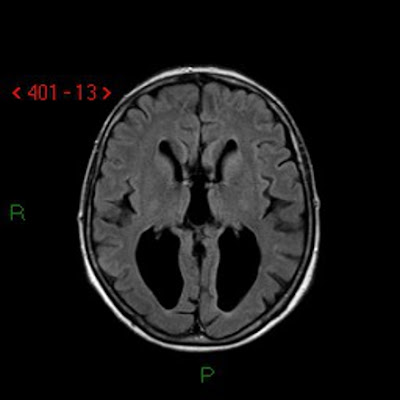

1-Colpocephaly means hydrocephalus or dilatation affecting posterior horns of the lateral ventricles more than anterior horns.

2-This condition occurs in the following diseases

-Agenesis of corpus callosum.

-Chiari malformation type 2.

| The above image is an example for colpocephaly where the posterior horns of the lateral ventricles are dilated more than the anterior horns. |